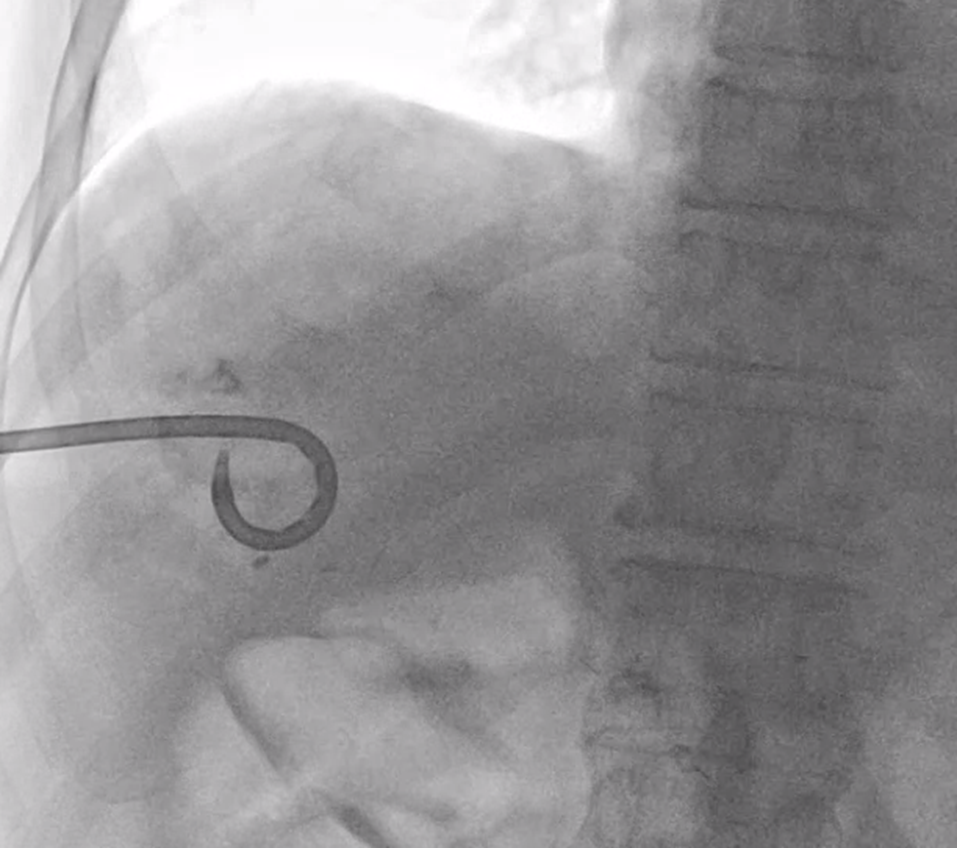

절개한 이후에는 초음파를 보면서 위에 제가 올린 Chiba needle 이라는 바늘로 목표한 병변을 찌릅니다.

이 바늘은 뚜껑같은 게 있어서 찌르고 난 뒤에 바늘 구멍을 통해 조영제를 주입할 수도 있고 매우 가느다란 철사(와이어)를 넣을 수도 있습니다.

그래서 바늘의 뒷 부분 뚜껑을 열고 조영제를 조금 주입해서 바늘이 목표한 병변 안으로 들어갔는지 확인합니다.

잘 들어갔다는 게 확인되면 아주 가느다란 철사를 넣습니다. 이 철사의 이름은 hair wire 입니다. 마치 머리카락 처럼 가느다랗기 때문이죠.

hair wire 를 넣은 뒤에는 introducer sheath 그 다음엔 앞서 말한 hair wire 보다 조금 굵은 철사가 들어갑니다.

마지막으로 굵은 철사를 따라 배액관이 들어갑니다.